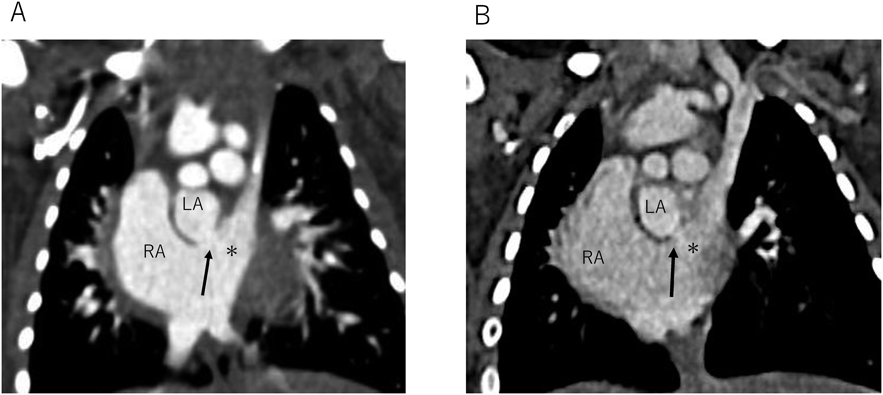

致命的となりうるunroofed coronary sinusの自然閉鎖を認めた僧帽弁閉鎖合併単心室例Spontaneous Closure of a Potentially Fatal Unroofed Coronary Sinus in a Case of Mitral Valve Atresia with a Single Ventricle